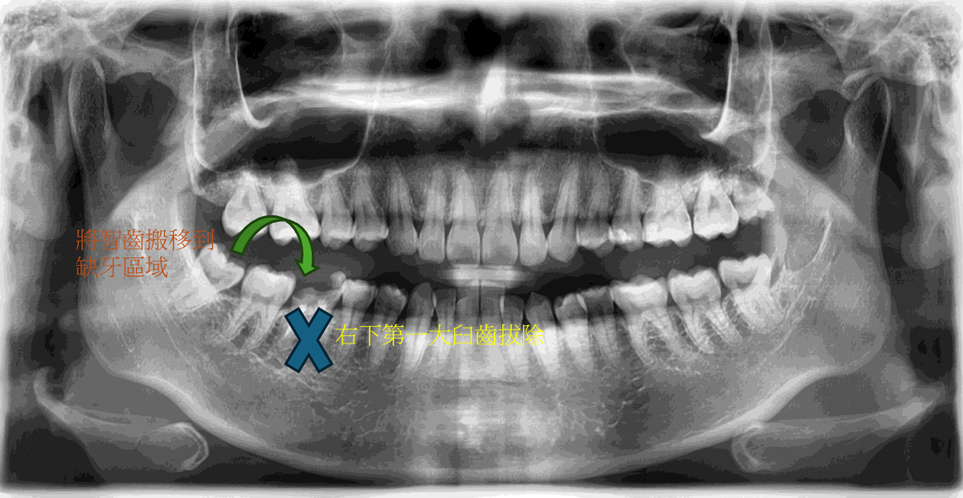

治療計畫

右下第一大臼齒拔除, 將右下智齒移植到缺牙區域